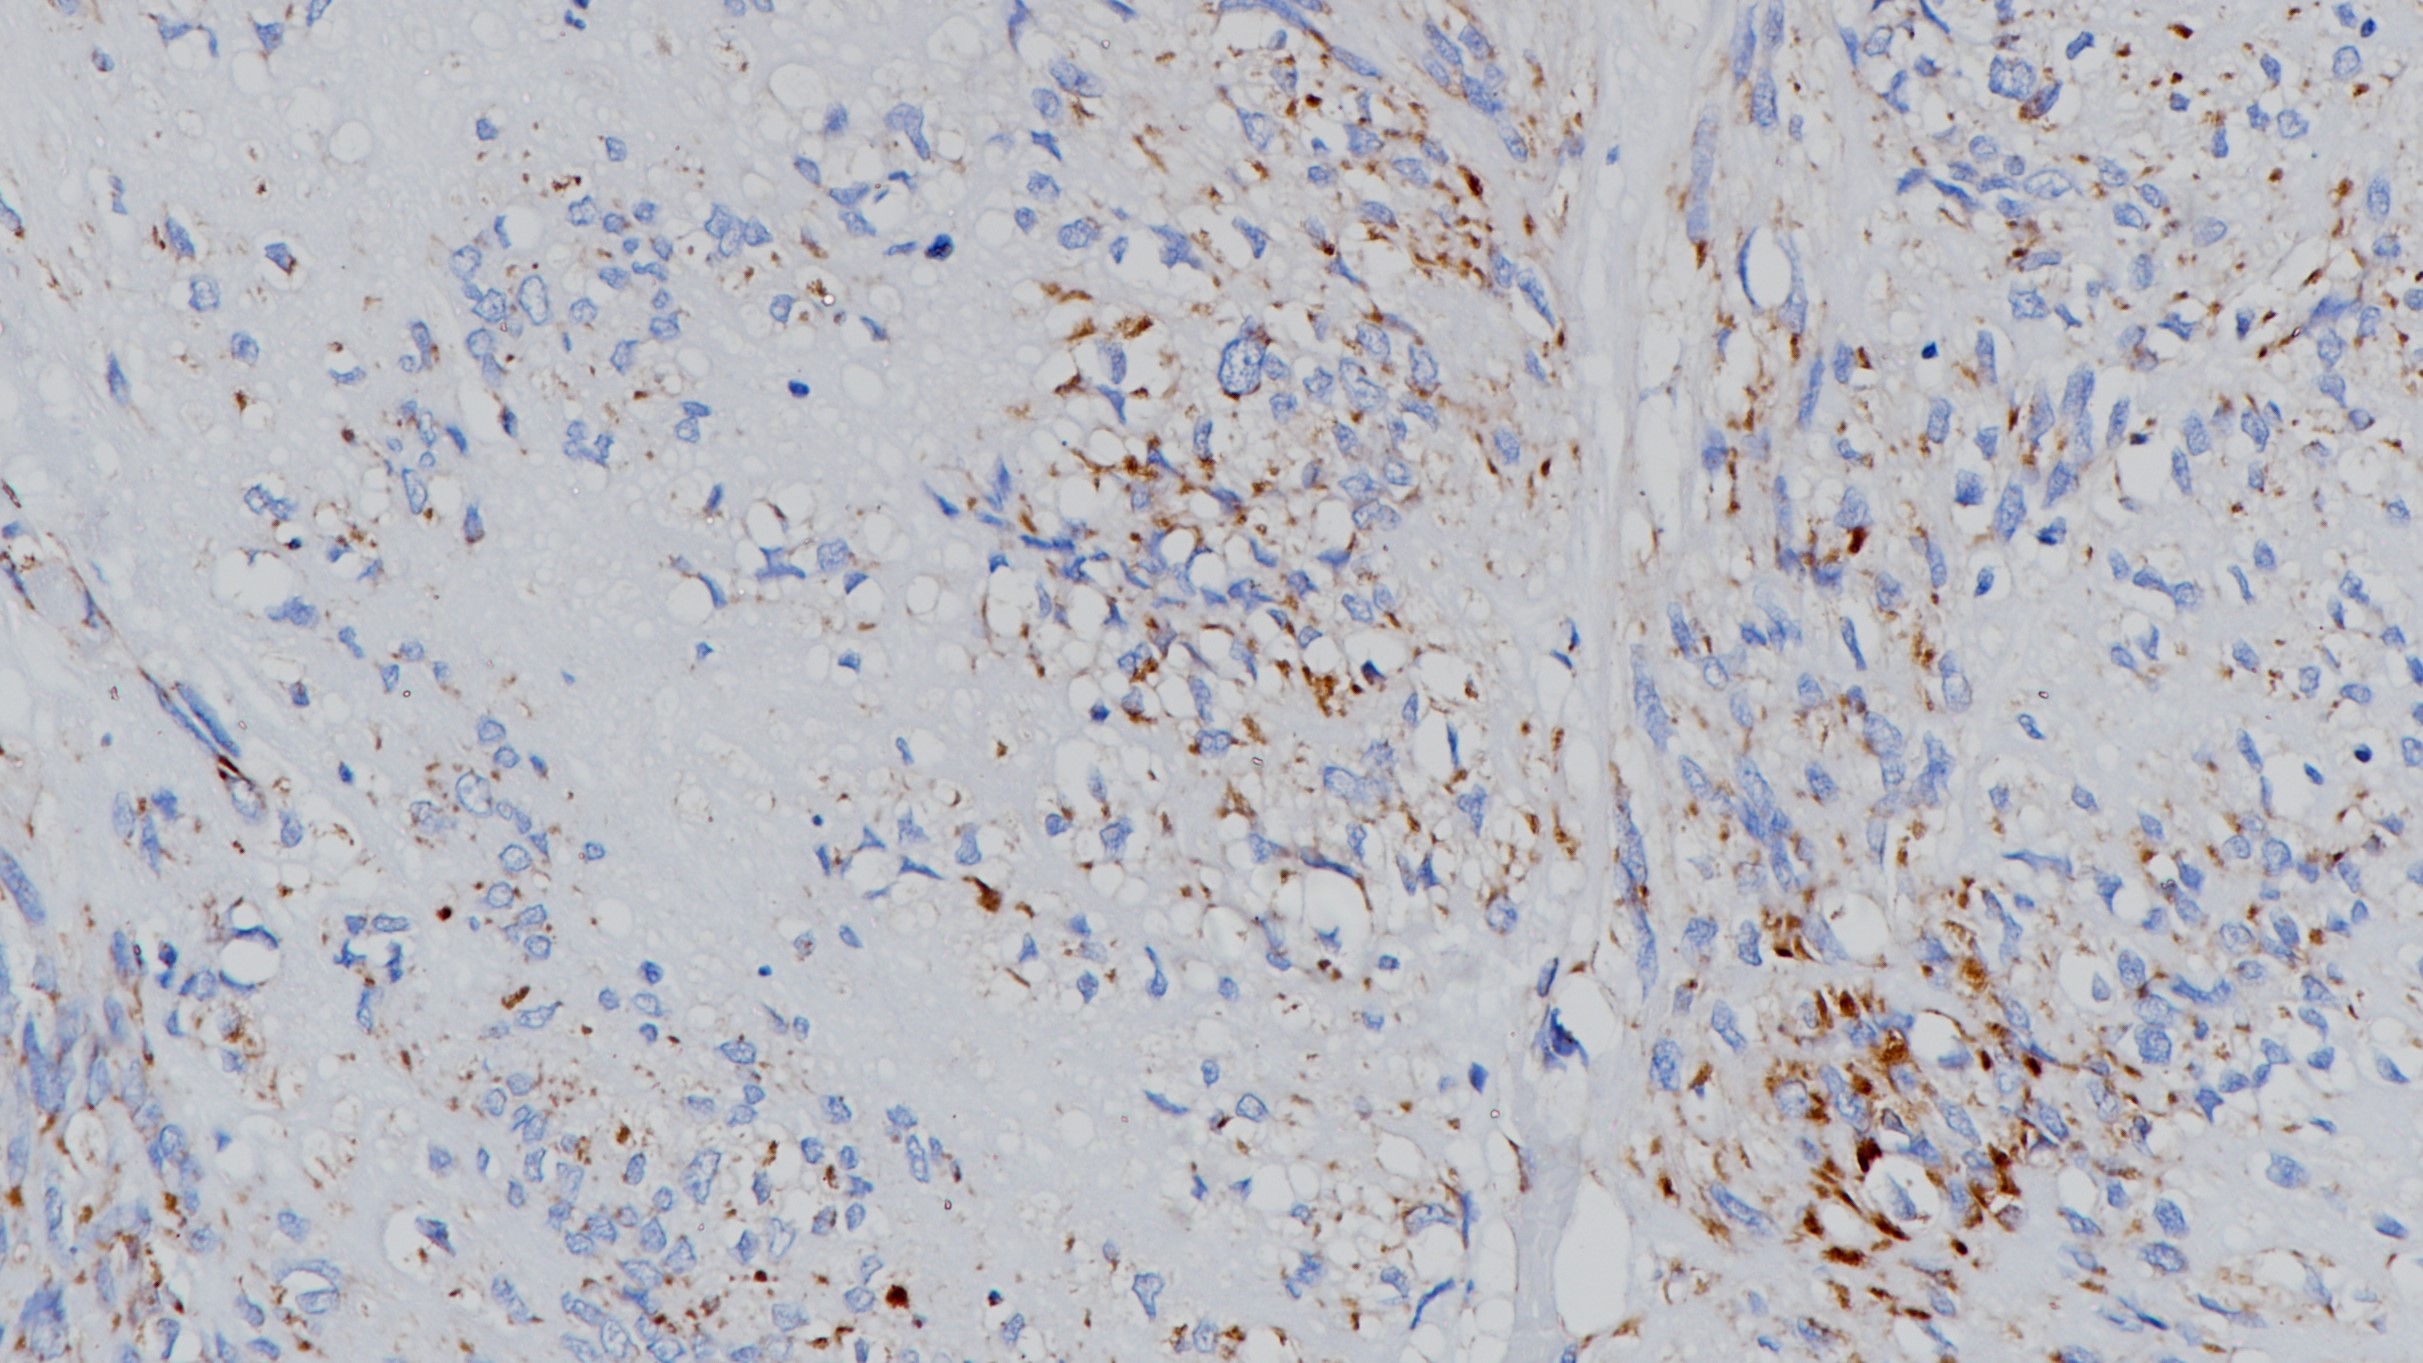

SDHB表达缺失的胃肠道间质瘤SDHB(BP6160)染色

琥珀酸脱氢酶 (Succinate dehydrogenase,SDH) 也称复合体 II 或琥珀酸:醌氧化还原酶,位于线粒体内膜,在三羧酸循环中可将琥珀酸转换成延胡索酸。SDH由4个亚基(A,B,C,D)组成,任何一个亚基发生突变将导致不稳定和复合体功能丧失。SDH各亚单位的突变均可导致SDHB蛋白缺失表达,故可用SDHB鉴定SDH缺陷型GIST。研究发现部分嗜铬细胞瘤(副节瘤)和肾细胞癌中存在SDHB突变。